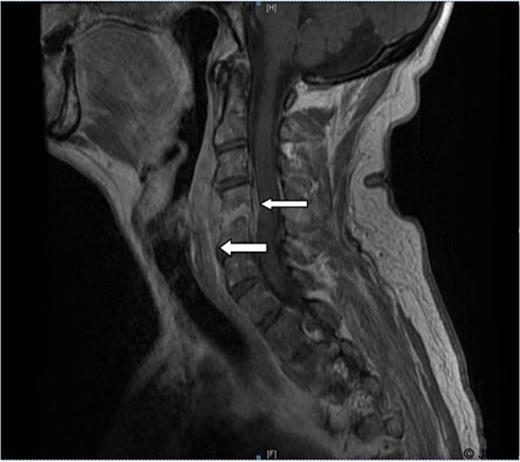

A 68 years old retired tennis coach was urgently admitted under the care of the ENT team following an alarming outpatient MRI scan result. The patient was referred with a six weeks history of progressive difficulty swallowing solids. Initially the patient was seen by his GP due to neck pain after riding his bicycle. It was clinically diagnosed as whiplash and treated successfully with analgesia and physiotherapy for 5 weeks. No history of URTI or trauma was reported. However, progressively the patient developed difficulties swallowing solids and described an uncomfortable “lump in his throat” sensation. The patient was, at all times apyrexial and his ENT examination was unremarkable except for limited extension of his neck and raised inflammatory markers. Due to these clinical findings, an urgent MRI neck scan with contrast was requested showing an extensive retro-pharyngeal enhancing collection associated to an epidural collection extending from C2 to C5/6. This collection indented the cord, particularly on the right. In addition, there was enhancement of the C4 and C5 vertebral bodies consistent with osteomyelitis (Figure 1 & 2).

Sagittal T1 image. There is an extensive retro-pharyngeal enhancing collection. In addition there is an epidural collection extending from C2 to C5/6.